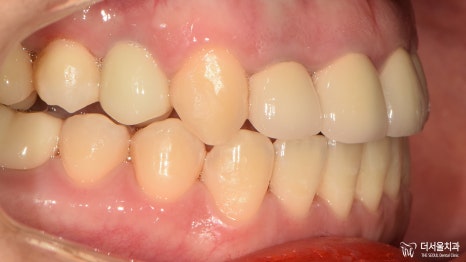

이전과는 달리 딱 봐도 고른 치열이 눈에 띕니다.

가지런한 치아와 상실된 기능 회복으로

만족, 대만족을 하셨던 환자분^__^

교정 과 임플란트 ,

둘의 합(合) 정말 놀랍지 않나요?ㅎㅎ

지금까지 20대 여성 교정 과 임플란트 ,

약 1년 반의 여정이었습니다.